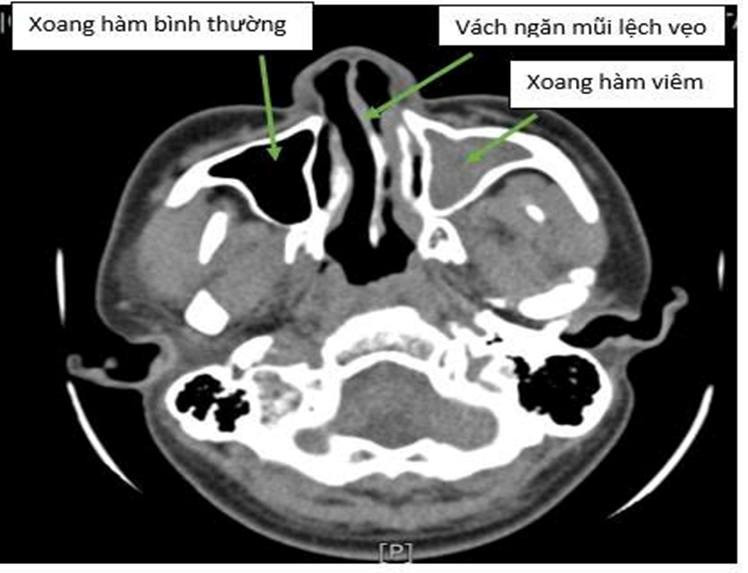

Nhưng khi đến khám tại Trung tâm Y tế thị xã Quảng Yên, anh mới bất ngờ: Kết quả nội soi mũi họng cho thấy vách ngăn mũi bị vẹo nặng, chèn ép một bên hốc mũi, gây nghẹt thở, ngủ ngáy, đau đầu, giảm khứu giác… nguy cơ lâu dài gây viêm xoang mạn, viêm mũi dị ứng.

Hình ảnh vẹo vách ngăn mũi trên nội soi - Ảnh BVCC